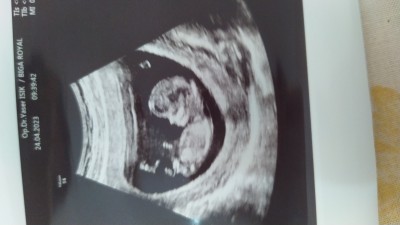

12. Haftadayım doktor göremedi cinsiyeti çok merak ediyorum ☺️

Aynen erkek bnce:)